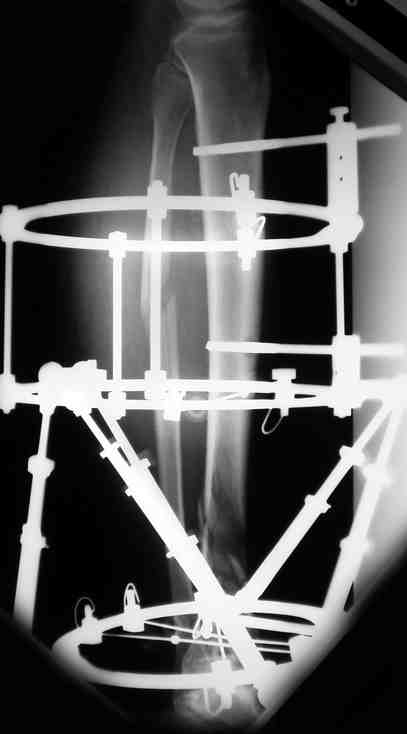

Выше представлены рентгенограммы открытого оскольчатого перелома нижней трети голени

X-rays of Compound Comminuted # Distal/3 Lt Tibia

Операционные снимки перед и после наложения аппарата Илизарова

In operation room before and after Ilizarov apparatus has been applied

Послеоперационные рентгенограммы

Postoperative X-rays

В нижнем ряду представлены рентгенограммы после окончательной репозиции.

And final reduction after Hexapod program has been finished